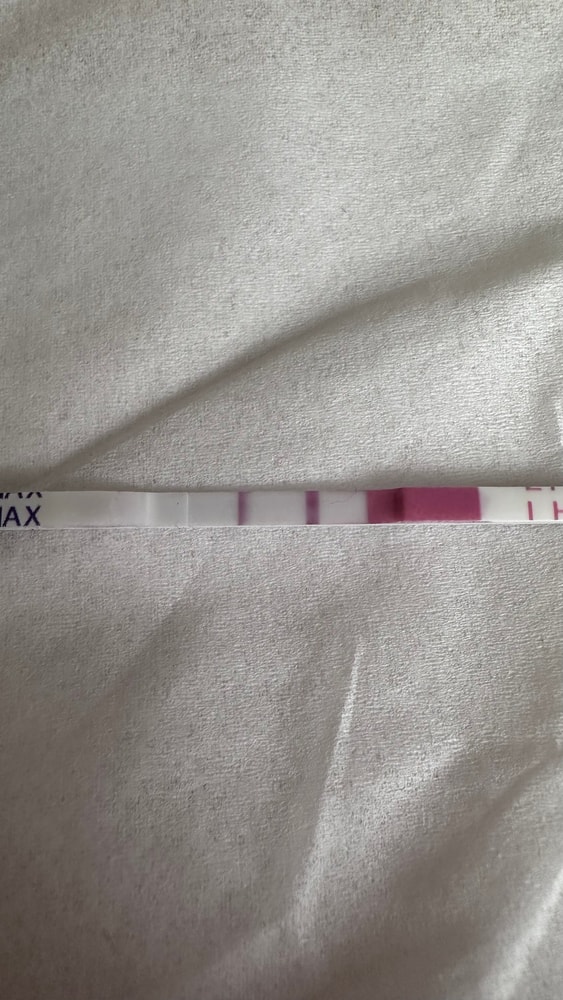

Тесты в студию🤗

Вот и мне отреагентили эти прекрасные тесты.

Что-то я понять не могу, свой организм вместе с тестами на овуляцию.

Тестик на овуляцию ярчает) я радуюсь как ребенок😂 овуляция с СПКЯ, большая редкость. Последняя была в январе (стимулированная), а предпоследняя в мае 2024 года. 20 д.ц и счаст